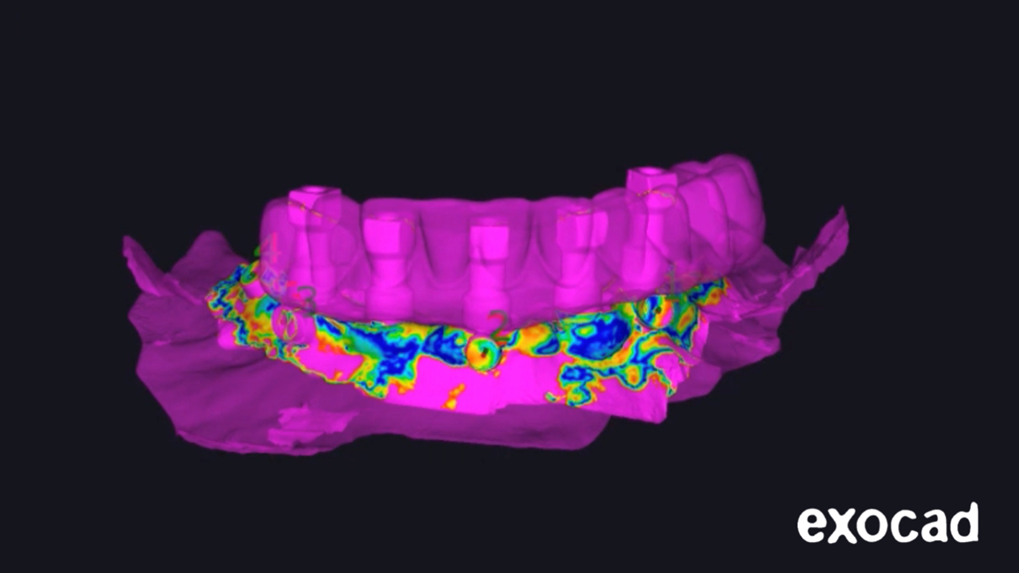

Após marcar os pontos, o próprio software CAD faz uma otimização do alinhamento dos arquivos digitais (Figura 7).